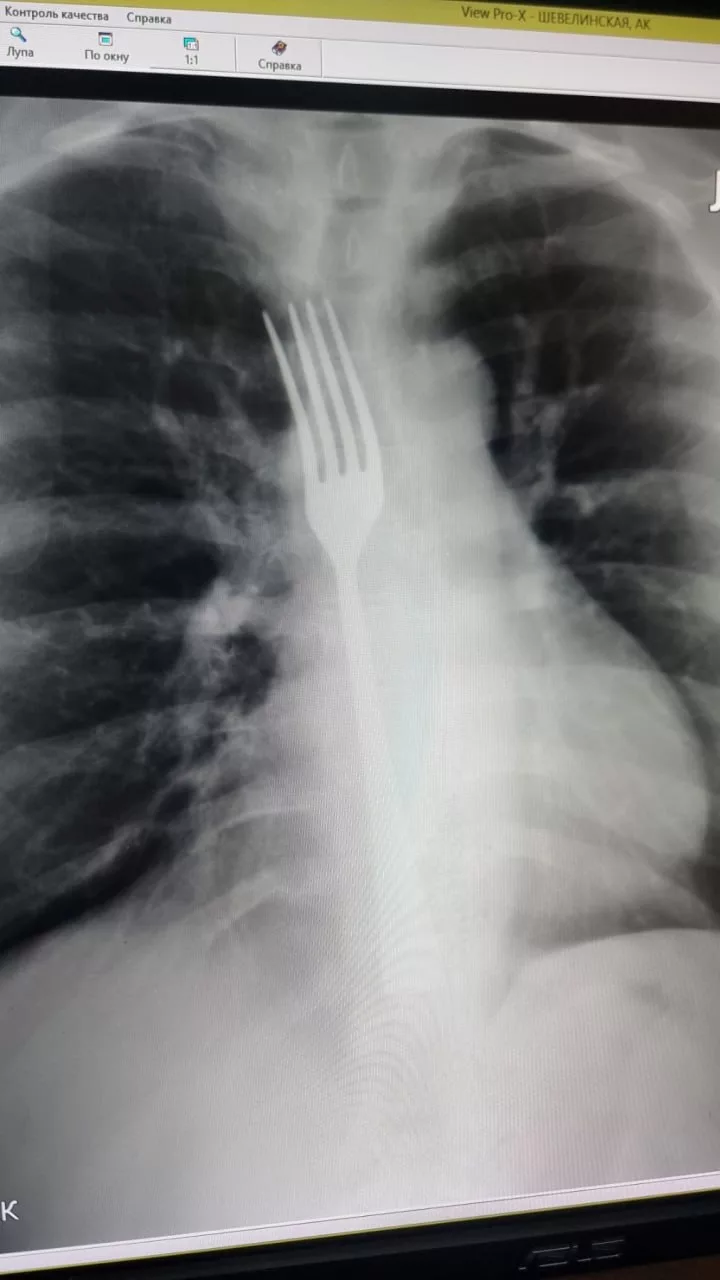

В Витебске женщине провели операцию после попытки вызвать рвоту вилкой

Жительницу Витебска увезли в больницу после того, как во время попытки вызвать рвоту она проглотила вилку. Предмет застрял в пищеводе, и без операции обойтись не удалось.

По информации медиков, у женщины заболел живот, и ей показалось, что «встал желудок». Она решила справиться сама и попыталась вызвать рвоту. Для этого использовала черенок вилки. В какой-то момент вилка соскользнула и ушла внутрь.

Женщину доставили в Витебская областная клиническая больница. После обследования её сразу направили в операционную.

Сначала под наркозом врачи попытались сместить вилку эндоскопом. Им удалось продвинуть её в желудок. После этого хирурги сделали разрез и извлекли предмет. Медики отмечают, что повезло: вилка не повредила пищевод и не застряла в его стенке. В таком случае операция была бы сложнее.